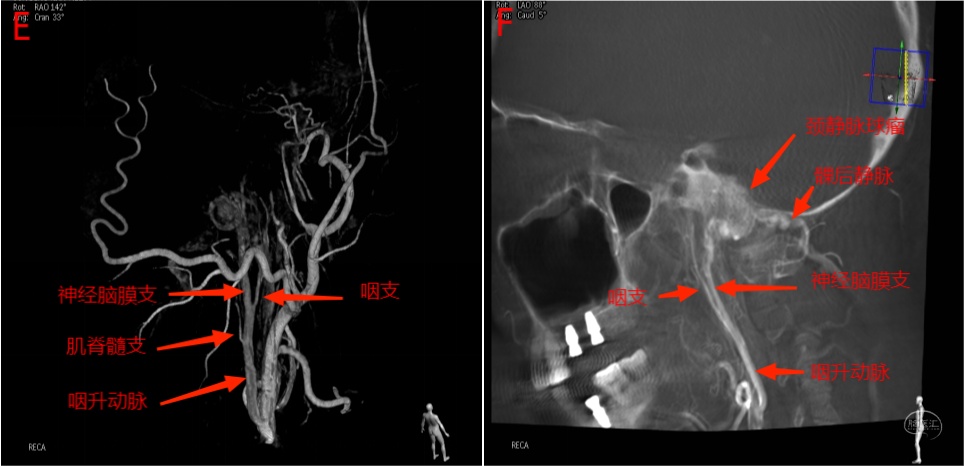

图18 E为3D成像,显示咽升动脉及神经脑膜支管径增粗,同时可见咽支及肌脊髓支。F为Xper-CT矢状位重建,显示咽升动脉、咽支、神经脑膜支、颈静脉球瘤和髁后静脉。

2.3 DSA解读影像3

右侧颈静脉球瘤患者进行术前造影及栓塞,咽升动脉神经脑膜支(颈静脉孔支)为主要供血动脉。

图16 A图为轴位增强MRI,显示右侧颈静脉孔内病变强化明显;B图为TOF轴位图像,右侧咽升动脉神经脑膜支位于右侧颈内动脉后内侧,管径明显增粗(左侧显示不清)。

图17 C为右侧颈总动脉侧位造影动脉早期,显示咽升动脉增粗,颈静脉球瘤血供丰富;D图为右侧颈总动脉侧位造影静脉期,颈静脉球瘤血流引流入颈内静脉和经髁后静脉引流入枕下静脉。